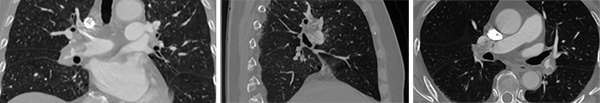

▲从左到右依次为:术前肺动脉CTA(冠状位)、术前肺动脉CTA(矢状位)、术前肺动脉CTA(轴位)

患者因突发胸闷、呼吸困难在外院就诊,检查显示其高敏肌钙蛋白及D-二聚体水平显著升高,初步诊断为急性心肌梗死。转至北京安贞医院后,经肺动脉CT血管造影(CTPA)等进一步检查,确诊为右肺动脉主干栓塞合并左肺动脉分支栓塞,同时发现下肢深静脉血栓。由于患者肺栓塞血栓负荷重且存在心肌损伤风险,传统治疗方案可能延误病因判断或增加出血风险。